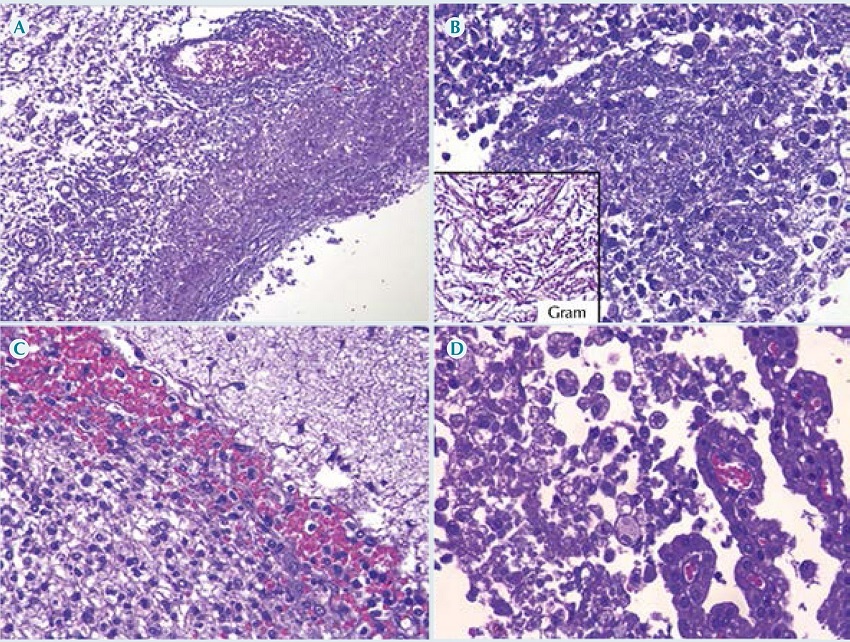

En la examinación histológica se observó una meningoependimocoroiditis piógena aguda (Figura 7) representada por un exudado supurativo con bacilos Gram negativos en ventrículos laterales, corroborada con el cultivo post mortem que reportó desarrollo de Pseudomonas aeruginosa en líquido cefalorraquídeo, pulmón, hígado y bazo. Los pulmones tenían una gran cantidad de macrófagos alveolares infectados por citomegalovirus (Figura 8). Además, se observaron cambios citopáticos virales por citomegalovirus en glándulas salivales, páncreas, suprarrenales, esófago, estómago, plexos coroides y médula espinal. Finalmente, se observaron datos anatómicos de choque: daño alveolar difuso en fase exudativa (membranas hialinas) con edema pulmonar agudo; miopatía visceral hipóxico-isquémica en corazón, tubo digestivo y vejiga; esteatosis hepática universal macro y microvesicular con colestasis leve; involución grave del timo (2 g vs. 20 g); dilatación vesical y dilataciones segmentarias del intestino delgado y colon sigmoides; nefromegalia bilateral (riñón izquierdo 65 g vs. 40 g, derecho 70 g vs. 44 g).